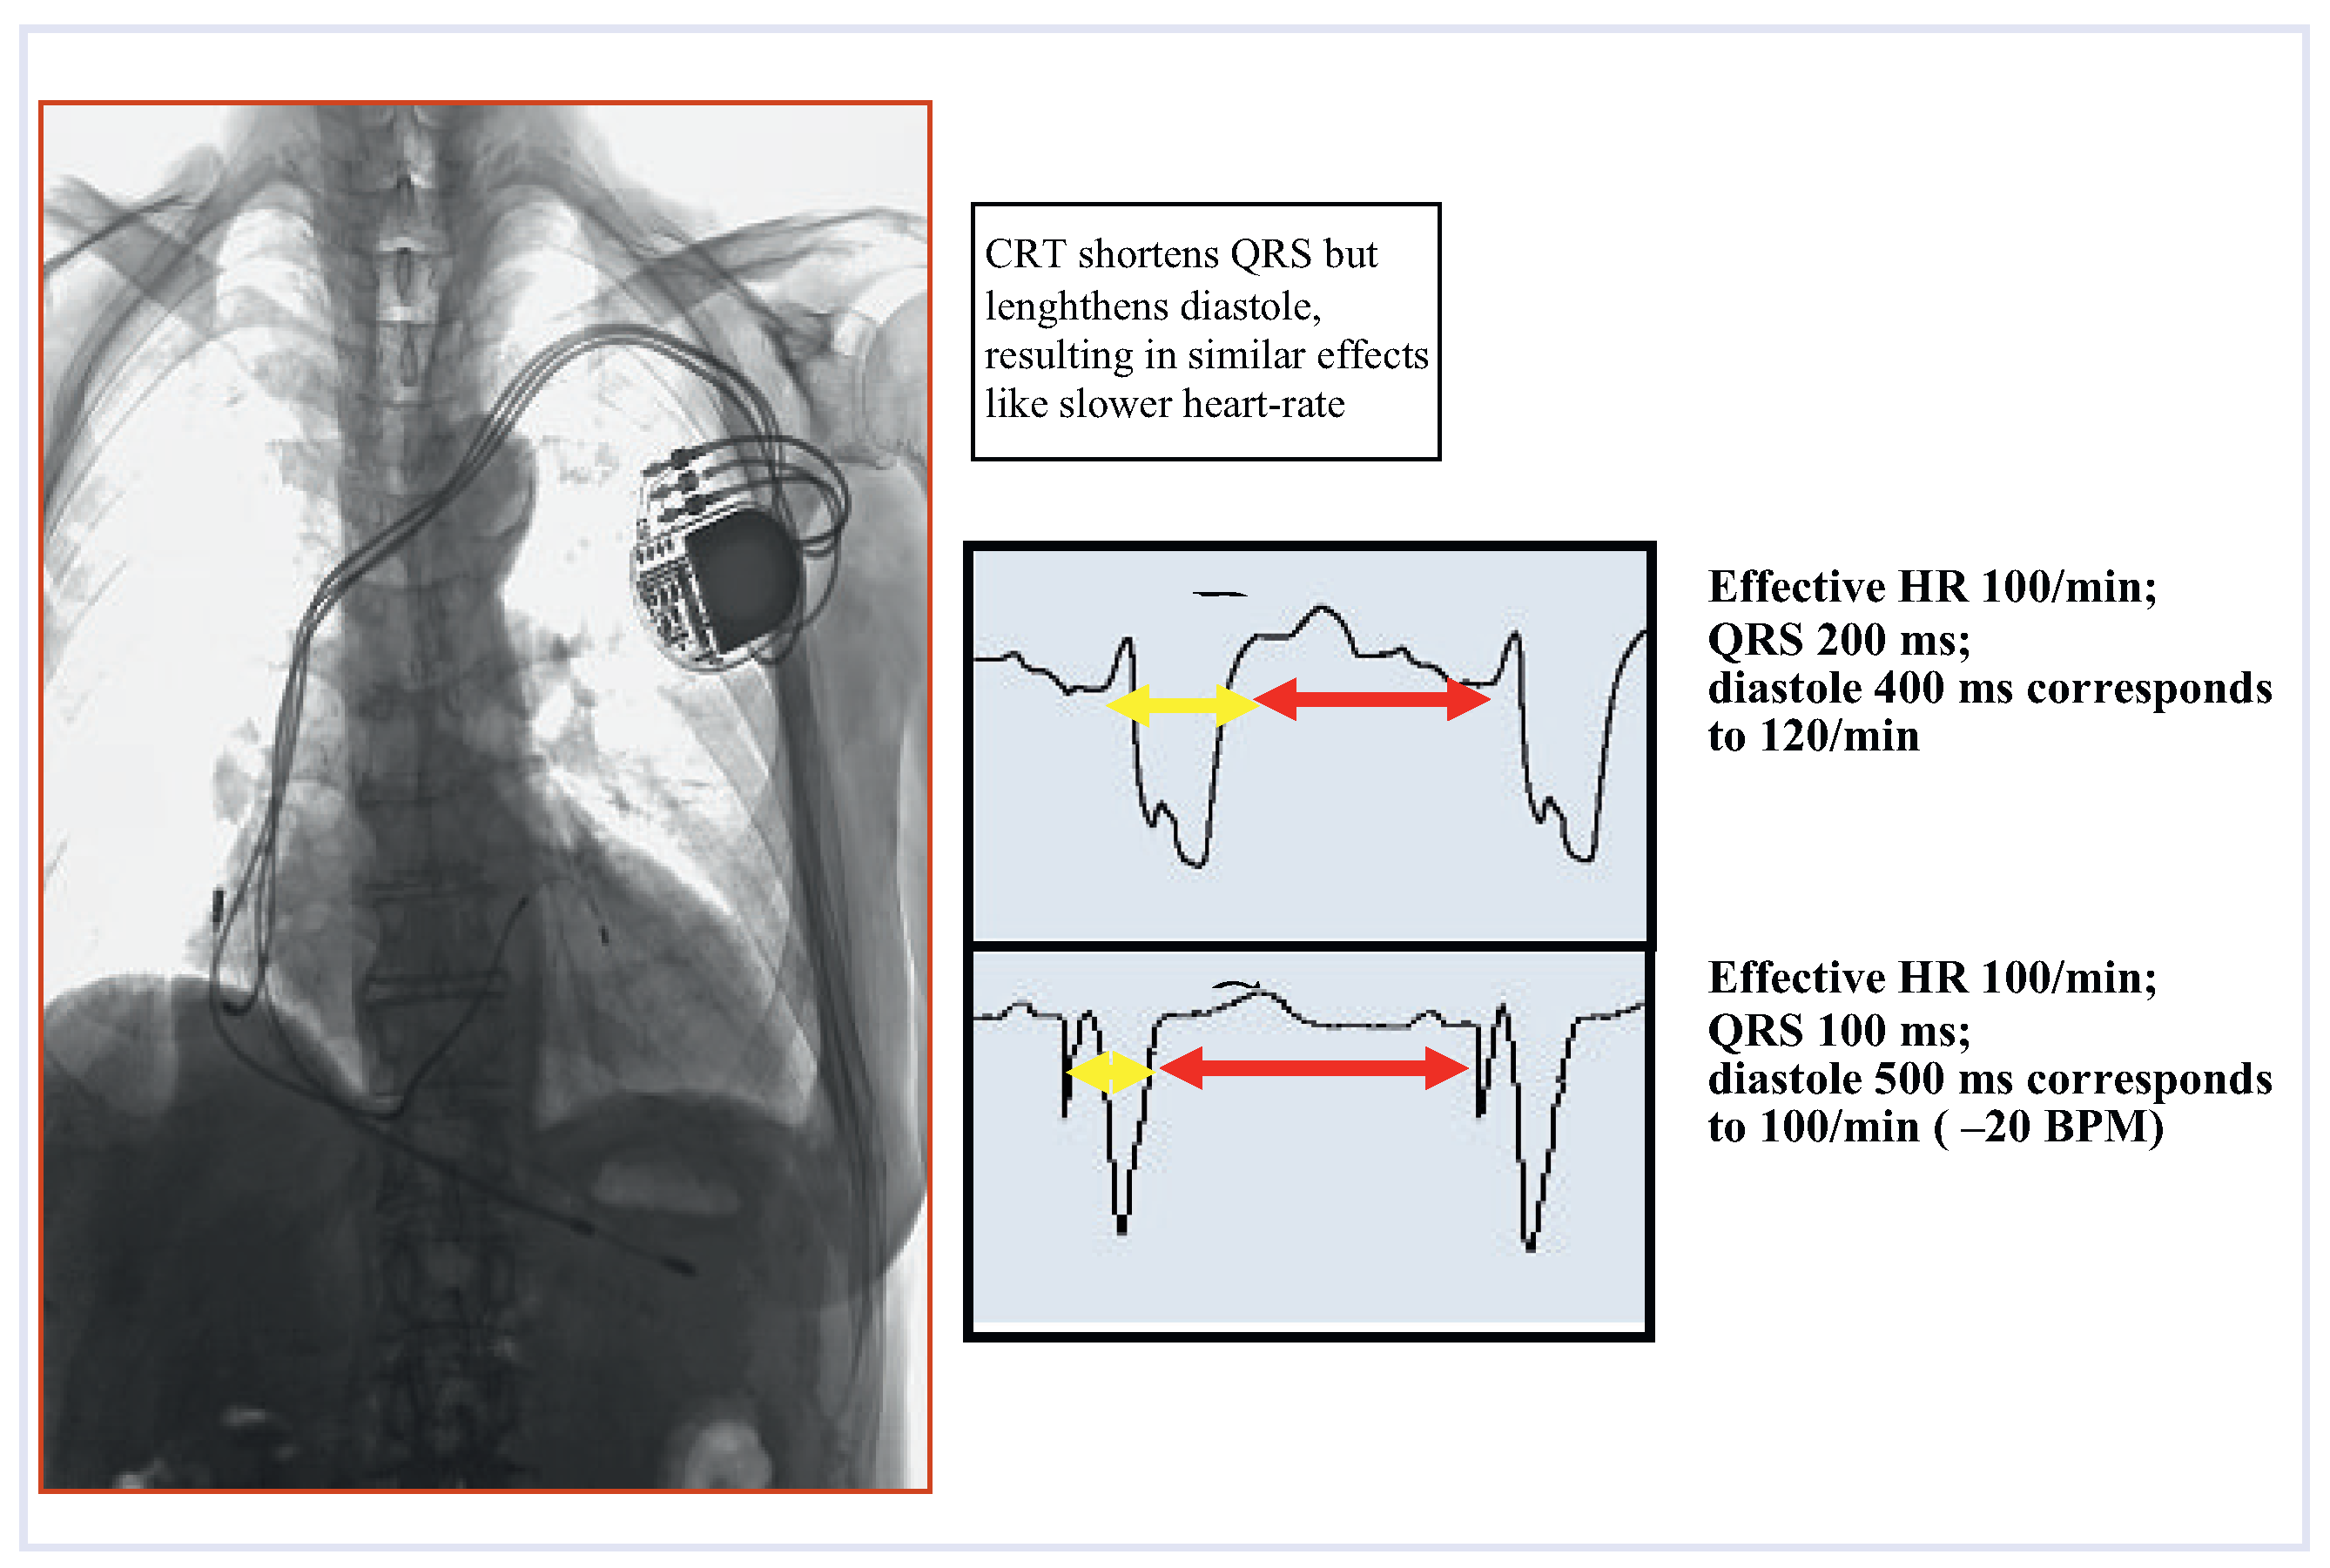

Resynchronisation

One common characteristic of many dilatative cardiomyopathies is a conduction delay, as evidenced by widening of the QRS complex. The latter generally points to the existence of an underlying mechanical dyssynchrony in ventricular contraction, but it may be difficult to know which came first, dyssynchrony or myopathy. Note however that a wide QRS does not necessarily imply underlying mechanical dyssynchrony, and that severe ventricular dysfunction may exist in the presence of normal QRS complexes [29]. Ventricular resynchronisation can improve heart function (ejection fraction, mitral regurgitation) but requires multifocal, at least right and left ventricular, pacing, e.g., with an electrode for left ventricular activation placed in a lateral cardiac vein through the coronary sinus or epicardial. Cardiac resynchronisation therapy (CRT) can allow for simultaneous contraction of the septal and free-left ventricular wall, and thus correct ventricular dyssynchrony with favourable effects on ventricular function (Figure 4 and Figure 5). After a proof of concept in a single patient [30] many reports and randomised controlled trials provided convincing evidence that CRT reflects a new approach to improvement of the failing heart muscle. Careful correlation between LBBB variation and mechanical contraction-sequence may lead to more specific selection of CRT candidates [13,29]. This may in part explain why individual response to cardiac resynchronization therapy may vary. However, numerous studies of heart failure populations have established the success of this therapeutic concept [31,32] firmly enough to justify its recommendation in the ESC guidelines for the treatment of heart failure [60], stating that cardiac resynchronisation therapy is indicated (evidence class IIA) in patients with a wide QRS complex >120 msec and an ejection fraction below 30–35%.

Figure 5.

The “mechanistic” concept of cardiac resynchronisation therapy (CRT). Note the LV electrode placed through the coronary sinus.

Areas of scientific uncertainty, such as indications for pacemaker therapy in early stages of heart failure, may still be open to discussion. To date, more than 100 studies of the effects of CRT are still ongoing. However, the concept that electrical stimulation is more than rhythm control is here to stay, and with CRT alone and combined with ICD the risk of heart failure events seems to be reduced even in relatively asymptomatic patients with a low ejection fraction and wide QRS complex [33,34,38].